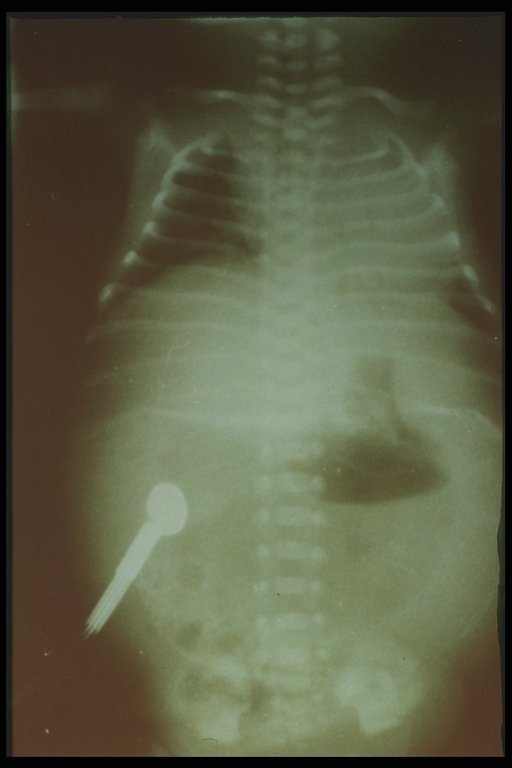

Meconium peritonitis. A classical plain abdominal X-ray demonstrates calcified extravasated meconium in the peritoneal cavity since fetal growth. Free air in the abdomen (football sign) is also noted